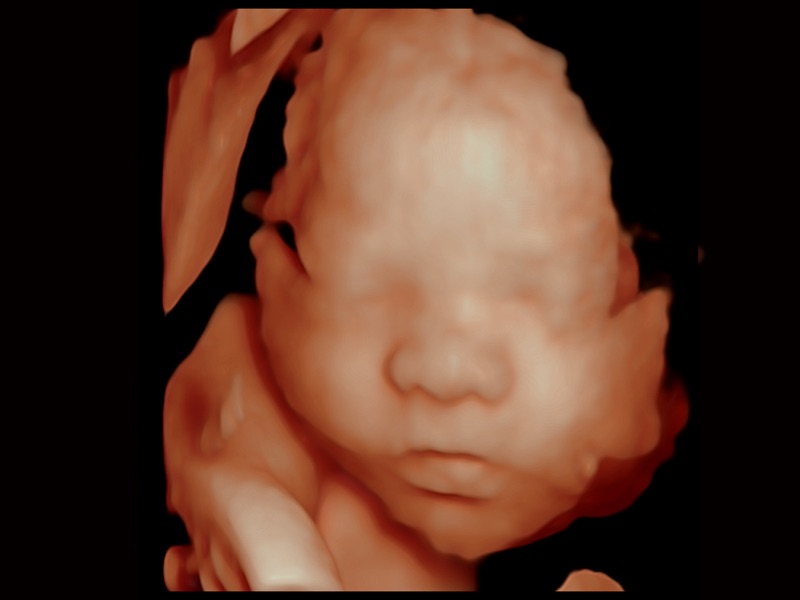

• 妇产科应用

• 光影成像

三维光影成像技术采用新型的渲染方式,增强边缘信息,使得轮显示清晰完整,为临床提供丰富、直观的三维结构,提供临床诊断准确性。

临床图